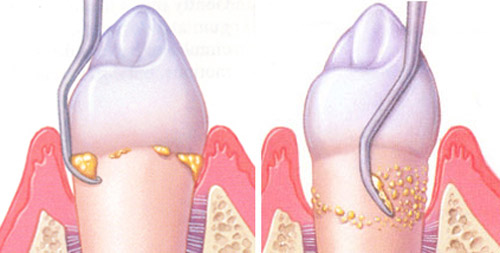

A betegséget gyakran emlegetik ínysorvadásként, mert előrehaladottabb esetekben gyakran többé-kevésbé visszahúzódik az íny is, azonban kevésbé pontatlan megfogalmazás lenne a csontsorvadás, ugyanis a csontvesztés a betegség előrehaladásának ez az egyik legfontosabb mérőfoka. Kicsit összetettebben szemlélve a problémát pont, hogy azzal az ínnyel van a probléma, ami alól eltűnik a csont, ugyanis a fog gyökere és az íny között mélyülő tasak egyre kevésbé tisztítható, így a betegséget okozó baktériumok egyre jobban el tudnak szaporodni, ezáltal egy ördögi kört fenntartva.

Ezt a betegséget baktériumok okozzák. Azonban ez nem egy idegen faj, a szájflórában normálisan, rendkívül kis mennyiségben jelenlevő baktériumok túlzó mértékű elszaporodása és dominánssá válása okozza a betegséget. Ezeket a baktériumokat másoknak nem tudja a beteg átadni, hiszen az ő szájukban is jelen vannak, így nem fertőző betegség. Azonban egy szájon belül egy tasak képes „megfertőzni” a többi a fogat és az implantátumot, ezért általában nem egy-egy fog betegségéről van szó, hanem az egész szájat szükséges gyógyítanunk.

A betegség gyógyítása a fogak felszínén jelenlevő baktériumflóra és a megtelepedésüket segítő érdes felületek, peremek mechanikus eltávolításán alapul, melyet ki lehet egészíteni fertőtlenítőszeres kezelésekkel, ritkán antibiotikumokkal. Szükség esetén a tasakokat sebészileg korrigáljuk, illetve sajnos a gyógyíthatatlan fogak eltávolítása is szükséges. Ezen gyógymód tudományos hátterét a Berni Egyetem Parodontológiai Tanszéke által képviselt, nemzetközi szinten elismert „berni koncepció” adja.